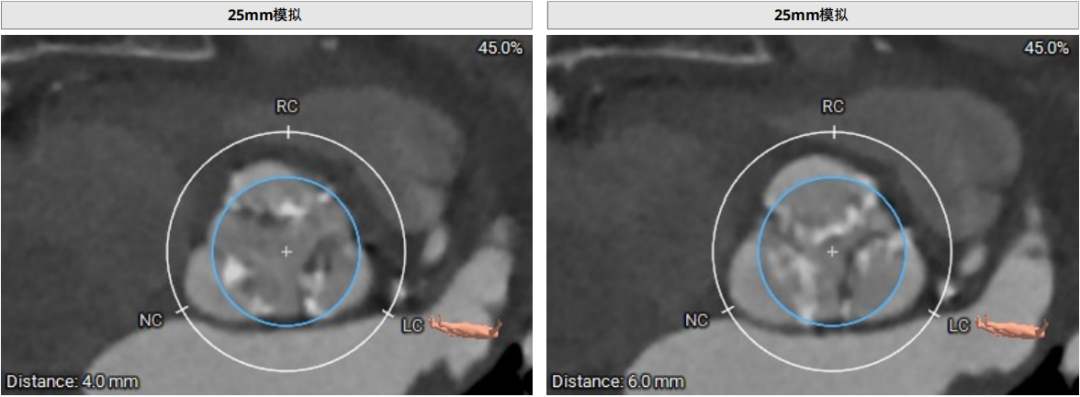

术前CT评估示

近日,中国人民解放军南部战区总医院王显悦教授、张本教授团队应用J-VALVE瓣膜完成一例高难度经心尖TAVI。患者为72岁男性,心脏超声示主动脉瓣重度狭窄伴轻度关闭不全,且二尖瓣中度狭窄。由于具有急性心力衰竭、高血压3级、肺气肿等其他疾病,且体重仅35公斤,对外科开胸手术耐受较差,风险极大,经过团队综合评估,决定行经心尖TAVI手术,拟植入25mm J-VALVE瓣膜。该患者存在升主动脉瓷化和左室流出道重度钙化,为手术增加了额外难度,术者团队凭借过硬的专业技能和细节处理能力,有效避免了术中可能存在的风险,并成功植入瓣膜。术后食道超声示无瓣周漏、无冠脉堵塞等并发症,患者症状明显缓解,手术顺利完成。

该患者升主动脉瓷化,左室流出道重度钙化。在TAVI手术过程中,导管和瓣膜的通过可能会对瓷化主动脉造成损伤,增加主动脉夹层、血管破裂等严重并发症风险;左室流出道的重度钙化会影响人工瓣膜与周围组织的贴合,使得瓣膜无法完全密封,从而增加瓣周漏的发生概率。